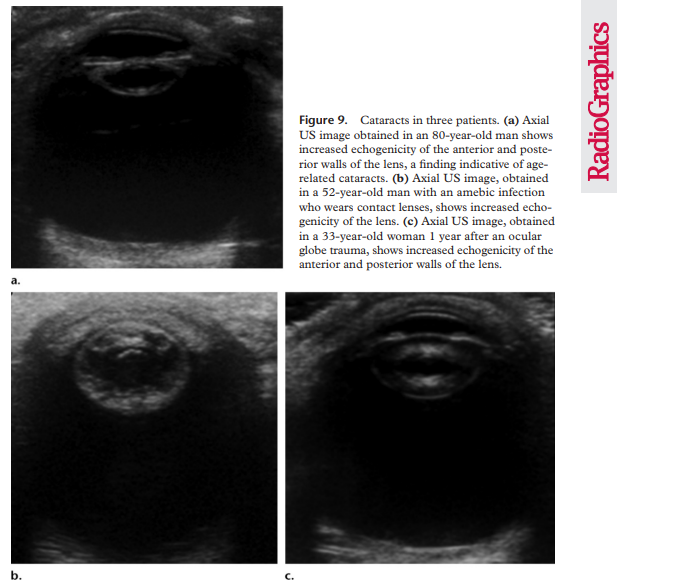

Cataract

When the lens becomes cloudy due to aging, trauma or radiation exposure this is referred to as a cataract. The normal lens on ultrasound echogenic at the edges and sonolucent everywhere else. On ultrasound a cataract can appear like irregular echoes or a heterogenous echotexture.